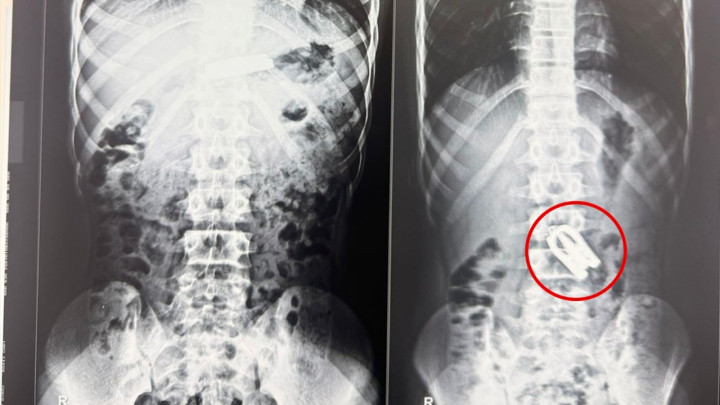

• १५ वर्षीय बालकले कैँची निलेपछी